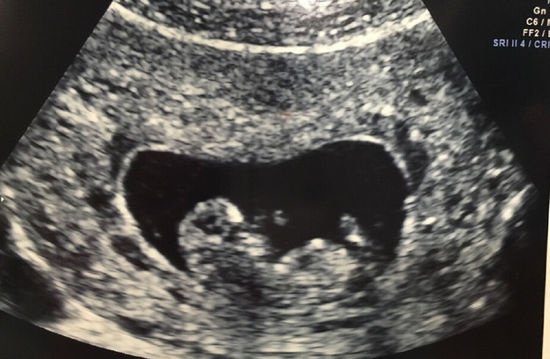

3、一般怀孕5周左右B超能看到孕囊在怀孕早期,受精卵着床后会逐渐发育形成孕囊通常情况下,停经5周左右时,通过经阴道超声检查,有可能发现宫腔内的孕囊这是由于经阴道超声检查相较于经腹部超声检查,具有更高的分辨率,能够更早地探测到宫腔内的微小结构然而,实际看到孕囊的时间并非绝对固定每个孕妇;怀孕后一般建议在6到8周进行B超检查以确认妊娠情况具体分析如下对于月经周期规律的女性,在末次月经后推5周即怀孕5周左右时,通过B超检查可能观察到宫内妊娠囊及胎心搏动此时若胚胎发育正常,可初步确认宫内妊娠但需注意,部分女性因排卵延迟或受孕时间较晚,胚胎着床时间可能推迟,导致妊娠囊。

4、怀孕最早在45周时通过B超能查出来具体说明如下最早时间通过阴道B超,最早在怀孕45周时可以发现非常小的像胎囊样的物质这里的45周是从末次月经的第1天开始算起典型胎囊出现时间通常在怀孕555周时,会出现典型的胎囊,此时卵黄囊也会出现,用B超可以基本上确定其是否为胎囊综合判断;因此,在进行B超检查以确认怀孕时,医生通常会结合孕妇的月经周期临床症状以及其他检查结果来做出综合判断如果孕妇对B超检查结果有疑问或担忧,建议及时咨询医生以获取专业的建议和指导总的来说,胚胎着床后通过B超检查多久能看出来怀孕是一个因人而异的问题一般来说,在怀孕5周左右可以通过阴道B超;怀孕后通常在停经56周可以通过B超检查观察到妊娠迹象具体时间受个体差异影响,需结合以下因素综合判断1 孕囊与胎芽的发育规律受精卵着床后,胚胎逐渐发育为孕囊停经5周左右,经阴道超声可能观察到宫腔内微小孕囊,但此时孕囊直径较小,结构尚不清晰至停经6周,多数孕妇可通过B超看到胎芽胚胎初步。